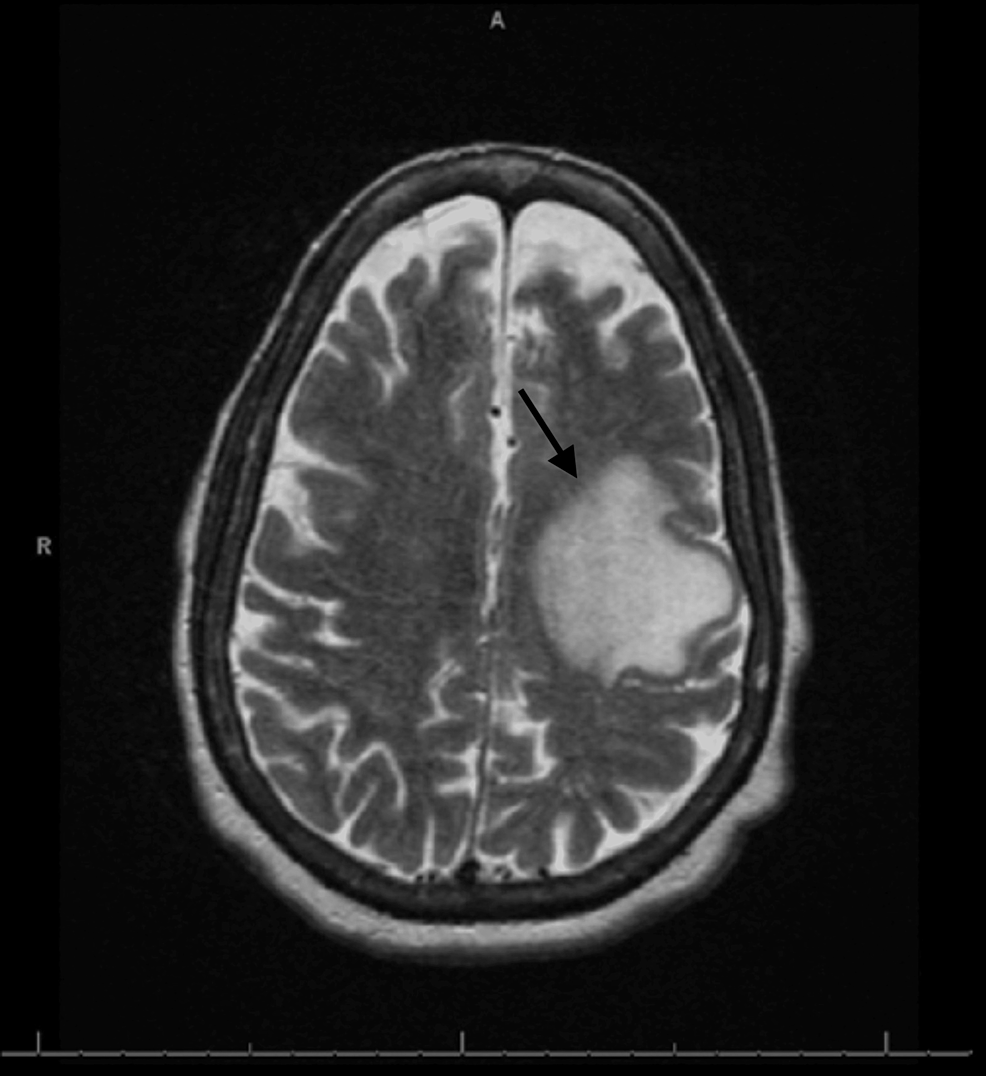

From www.cureus.com

Cureus Glioblastoma Multiforme in a Patient With Alpha1Antitrypsin Deficiency Alpha Beta Ratio Glioblastoma direct evidence that prostate tumors show high sensitivity to. The alpha/beta ratio for tumor. the alpha/beta ratio represents the dose, where cell killing from the linear and the quadratic components are equal. the selection of accurate lq parameters α, β and α/β is pivotal for a reliable estimate of radiation response. in addition, we employed an. Alpha Beta Ratio Glioblastoma.

From clinmedjournals.org

Concurrent Pituitary Adenoma and Intraventricular Glioblastoma Multiforme A Case Report and Alpha Beta Ratio Glioblastoma the selection of accurate lq parameters α, β and α/β is pivotal for a reliable estimate of radiation response. The alpha/beta ratio for tumor. the analysis confirms a high value for the α/b ratio. in addition, we employed an α estimate of 0.26 gy −1 and an α/β ratio of 8 gy based. direct evidence that. Alpha Beta Ratio Glioblastoma.

Cureus Glioblastoma Multiforme in a Patient With Alpha1Antitrypsin Deficiency Alpha Beta Ratio Glioblastoma The alpha/beta ratio for tumor. the selection of accurate lq parameters α, β and α/β is pivotal for a reliable estimate of radiation response. the alpha/beta ratio represents the dose, where cell killing from the linear and the quadratic components are equal. in addition, we employed an α estimate of 0.26 gy −1 and an α/β ratio. Alpha Beta Ratio Glioblastoma.